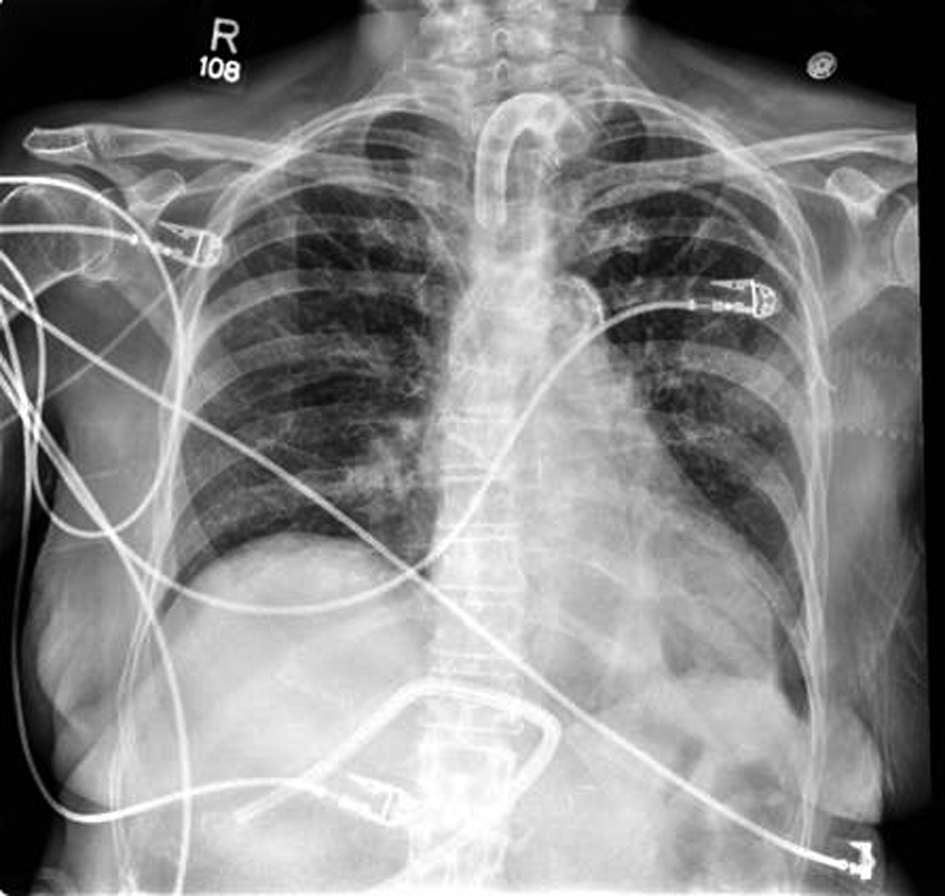

After surgery, the thoracic drain output dropped significantly. At the time of discharge, the output averaged 200 mL per day. The patient was eventually taken off TPN and switched to tube feeds. The patient was also weaned from the ventilator and was tolerating 24 hour tracheostomy collar. All intrathoracic drains were removed (Fig. 3). The patient was discharged to a rehabilitation facility where the patient was able to be de-cannulated and receive the physical therapy required.

![]() Click for large image | Figure 3. Chest X-Ray following ligation of thoracic duct and removal of drains, POD12. |